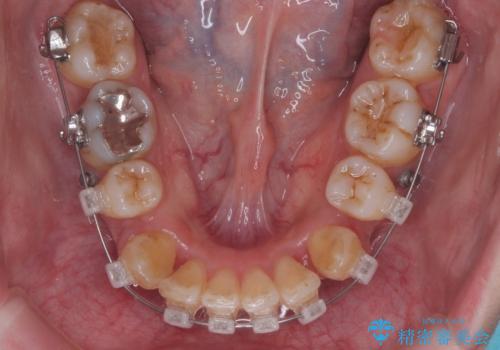

- 矯正装置

- ワイヤー矯正

- 治療期間

- 3年

- 治療回数

- 30回以上